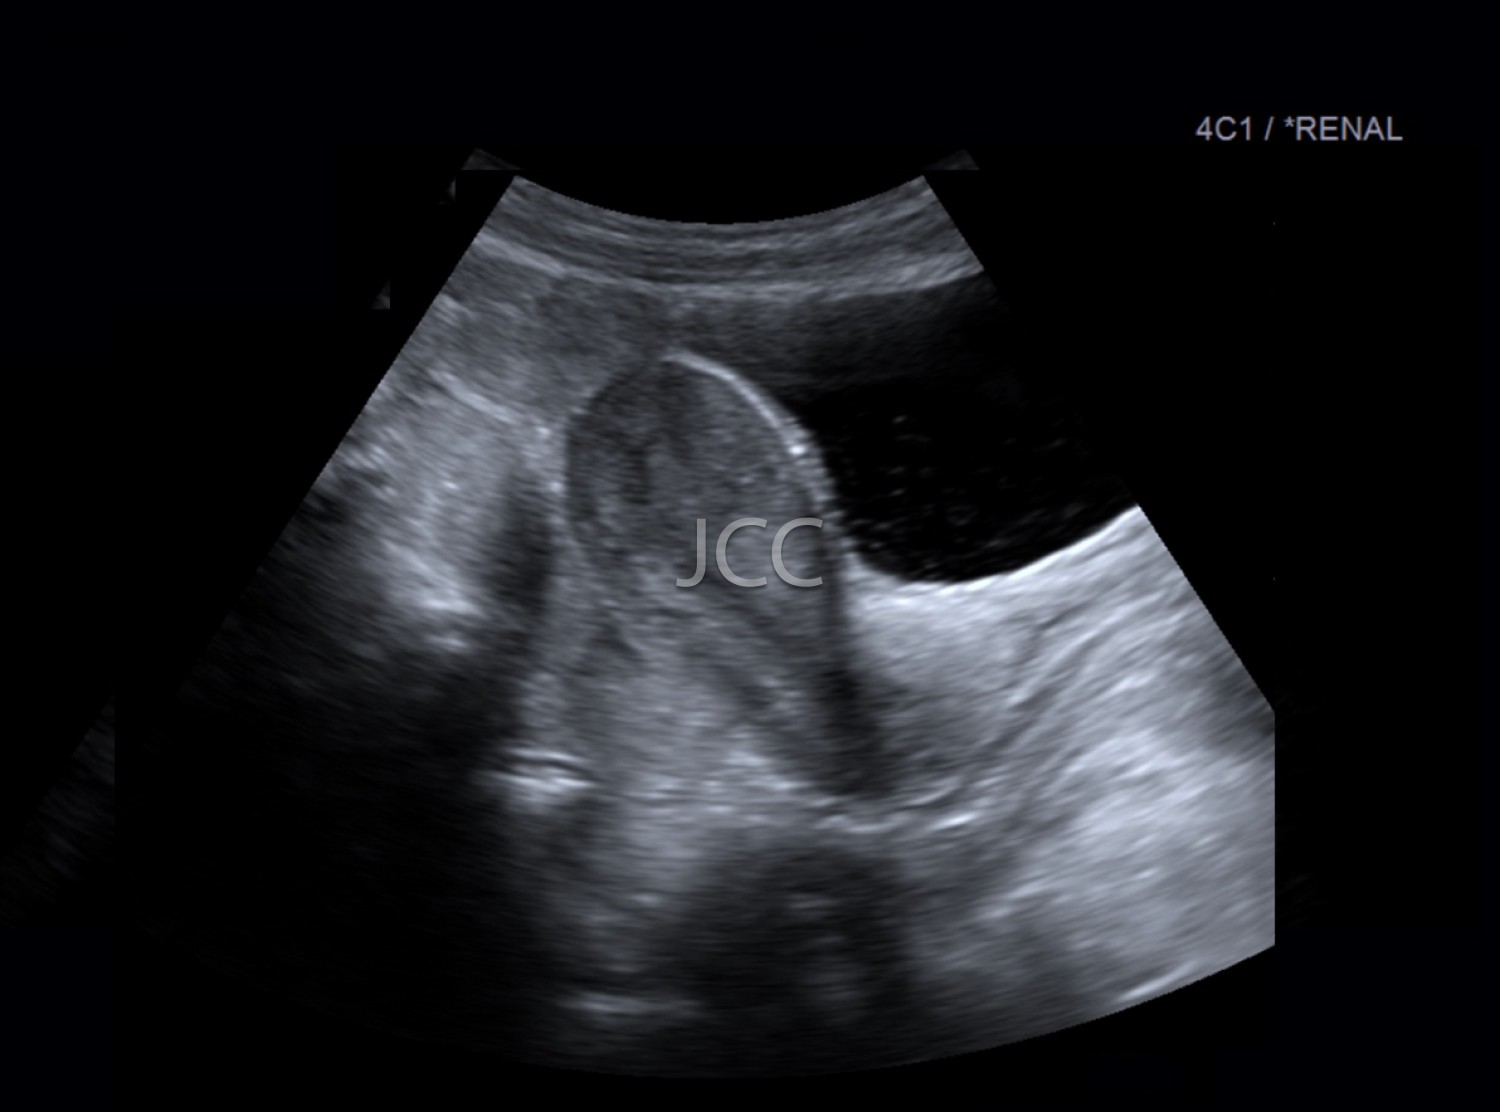

Descubra aqui os exames disponíveis nas clínicas do Grupo Dr. João Carlos Costa.

Marque aqui o seu exame sem sair do conforto de sua casa. Confirmamos em 48 horas.